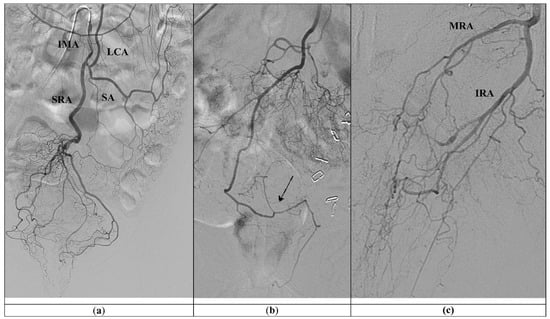

- Ferrer Puchol, M.D.; Esteban Hernández, E.; Blanco González, F.J.; Ramiro Gandia, R.; Solaz Solaz, J.; Pacheco Usmayo, A. Selective intra-arterial embolisation to treat haemorrhoids. Radiología 2020, 62, 313–319. [Google Scholar] [CrossRef]

| Ferrer puchol et al. [28] 2020 | Prospective case series | 20 patients: 18 with chronic pain and bleeding due to HD grade II and III, with contraindications to surgery and 2 needing urgent embolization | 90/83.4 | 300–500-μm PVA Particles and 2–3 mm coils | 1 episode of IMA dissection 3 episodes of rectal heaviness and pain |